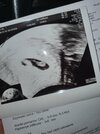

Mamy to 😍😍

Załączniki

• 03ed7b49-8c77-46ee-a88c-54834c53017e.jpg

03ed7b49-8c77-46ee-a88c-54834c53017e.jpg

56,7 KB · Wyświetleń: 145